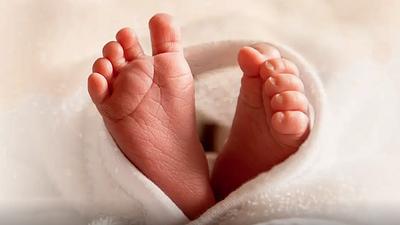

pezinho.jpg

Rio amplia teste do pezinho para detectar 54 doenças raras

06/06/2025, 10:44

De 2023 a 2024, foram realizados quase 250 mil exames em todo o Estado, o primeiro do país a oferecer o exame ampliado nos 92 municípios, passando de sete para 54 doenças rastreadas.